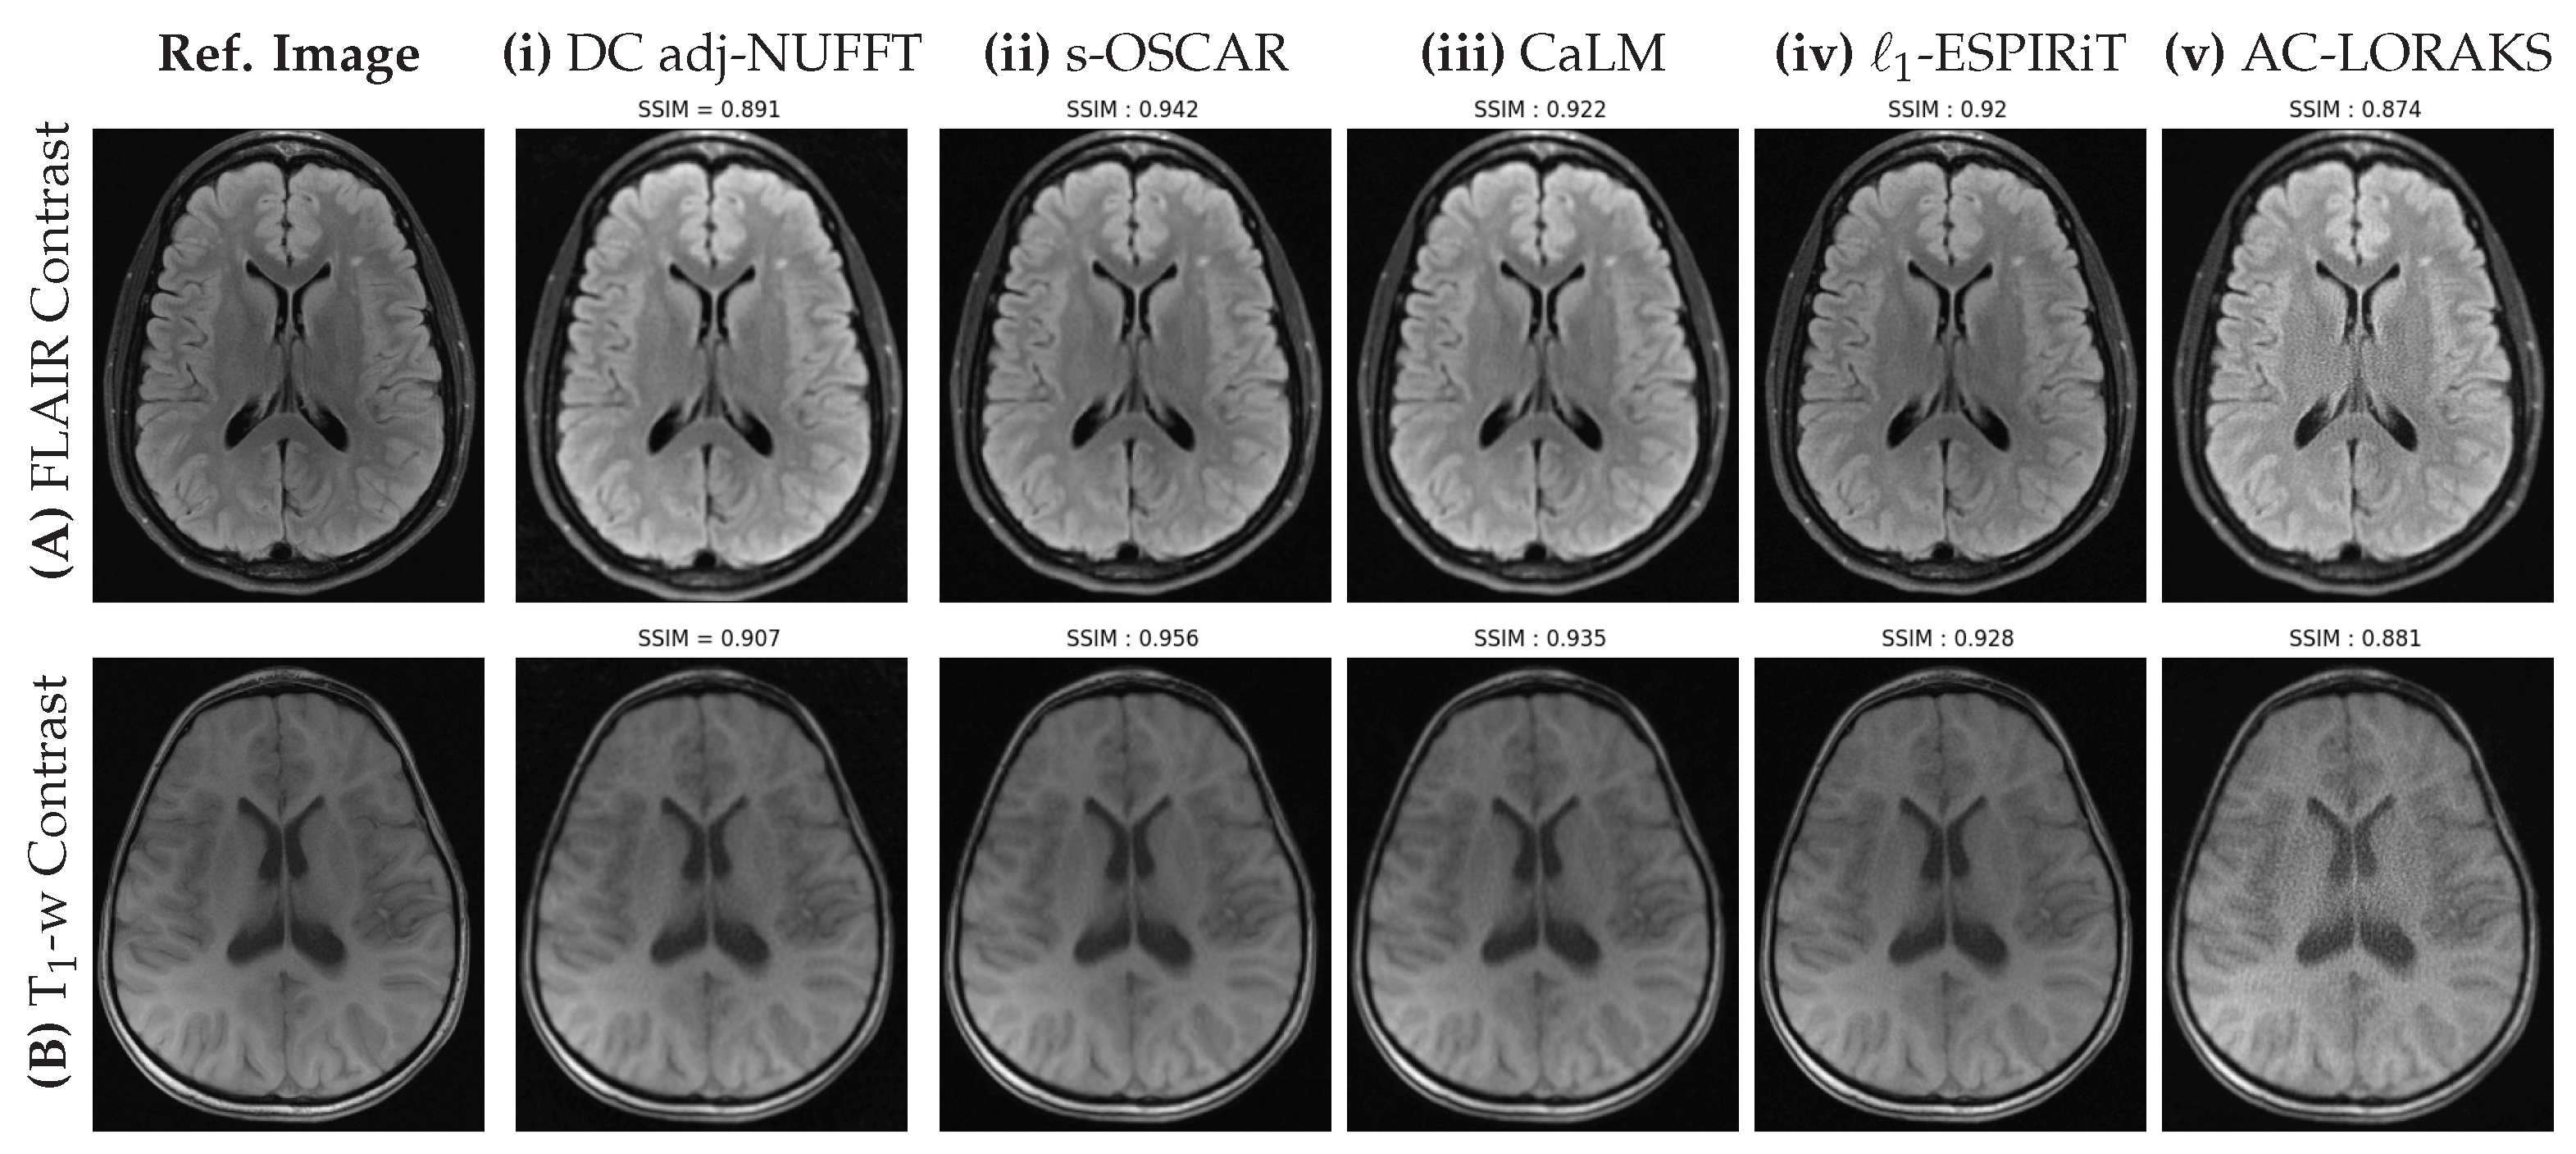

Figure 5.

Retrospective results for a single slice of FLAIR (top row) and T1 weighted (bottom row) images of the brain fastMRI data set obtained using the Non-Cartesian sampling pattern shown in Figure 3B with and . The fully sampled Cartesian reference and the different methods (Density Compensated (DC) adjoint NUFFT, s-OSCAR, CaLM, L1-ESPiRIT and AC-LORAKS) are shown from left to right and the SSIM scores are indicated to reflect the performance of each method.

In Figure 5, our first observation is that all methods perform better in this non-Cartesian retrospective under-sampling study compared to the Cartesian one. The reason is quite obvious and due to the use of a lower under-sampling factor () in this non-Cartesian setting as compared the 4-fold under-sampling in the Cartesian study. Although the UF is lower, this corresponds to a shorter scan time as the factor that mainly affects the acquisition time is the number of shots, irrespective of the number of samples per shot. This is a direct illustration of the benefit of implementing non-Cartesian encoding schemes. When comparing the different methods, it is worth noting the poor behavior of AC-LORAKS that reports lower SSIM scores and the wrong contrast. This results from the gridding step used before the application of the AC-LORAKS reconstruction method and the lack of density compensation as SPARKLING sampling implements variable density sampling. DC adjoint-NUFFT provides a better SSIM index than AC-LORAKS but faces similar contrast issues, especially on the FLAIR image. In contrast, all other competing techniques are pretty close and report SSIM scores larger than or equal to 0.92. Still the s-OSCAR provides the best contrast and less artifacts in the images.